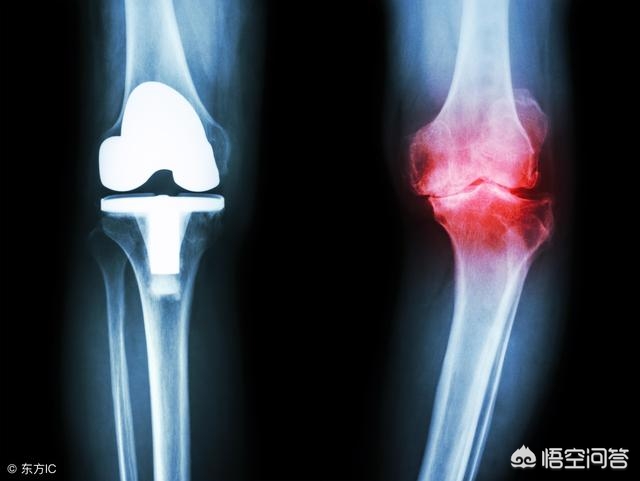

首先膝关节由三块骨头组成---股骨、胫骨、髌骨,三块骨头之间的关节面被一层关节软骨覆盖,就跟我们平时吃的“猪筒骨”一样,关节软骨像海绵软垫一样,起着吸收震荡,减压的作用。随着年纪的增长,关节软骨慢慢磨损,厚度也越来越薄。磨损下来的“碎屑”就很容易诱发关节炎的发生;最后,关节软骨部分磨损甚至全磨损完了,骨头磨骨头,就会出现剧烈的疼痛!

关节软骨这块“软垫”没有了之后,失去了软骨的防震减压功能,膝关节面受到的压力就会变大;人体是个神奇的生物体,为了保证膝关节在相同压力下或者更大的压力下保持压强不便,那么就只有增加受力面积了,骨头慢慢就开始增生了,“骨刺”就长出来了,长出来的骨刺,增加了膝关节的受力面积,因此可以在一定程度上保持膝关节压强波动不会过大。

膝关节周围骨质增生必然会将其周围的软组织、肌腱“顶起来”,导致膝关节周围软组织失衡,久而久之软组织、肌腱就会出现一定程度的松弛或者是挛缩,进一步导致膝关节的不稳定,甚至出现膝关节畸形,关节不稳定了,必然就伴随着关节疼痛,加大手术难度!对于这种病人,手术后清楚了骨质增生,术后也可能存在关节周围软组织失衡,恢复效果也可能较差!